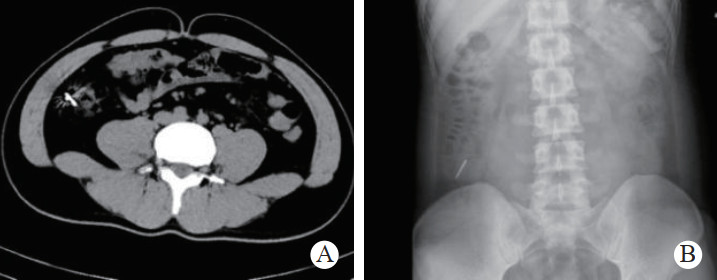

1 一般资料患者,男性,32岁,职员,因“误吞金属钉状物7 d”就诊。患者7 d前误吞入金属钉状物一根(大小约3 cm),患者无明显不适症状,未诊治。4 d前出现下腹隐痛,行急诊全腹CT检查,见图 1,行急诊胃镜检查未见明显异物。后复查腹部CT示异物进入小肠内(图 2),普外科会诊建议随访。2 d前复查腹部CT(图 3),继续保守治疗。1 d前患者为行异物取出入院,复查腹部CT可见异物至结肠内(图 4)。急诊予以聚乙二醇电解质散导泻清肠,行无痛肠镜下异物取出术。本文已通过本院伦理委员会审批,伦理审批号为:(2021)伦审研第(0252)号,并通过免除知情同意申请。完善术前检查,进行药物导泻清肠时,关注患者有无腹痛等现象,以免因服用药物清肠,肠蠕动加快,尖锐异物在消化道内随蠕动前行,尖端嵌插在肠壁中而停滞不前,并随着后方内容物的推进,加深尖锐异物刺入肠壁,最终导致穿孔及出血的发生。本例患者安置在独立单人间进行肠道准备,不定时进行腹部查体及观察排泄物的性状,早期发现穿孔、出血指征,以便尽早进行外科手术干预。与此同时,内镜中心医护人员联合外科、放射科、麻醉科医生制定诊疗方案,若发生此类情况,立即予急诊行腹部X线或CT检查,一旦确定出现穿孔或出血等情况,即刻行急诊手术治疗。

| 图 1 腹部CT示胃窦幽门部尖锐异物 |